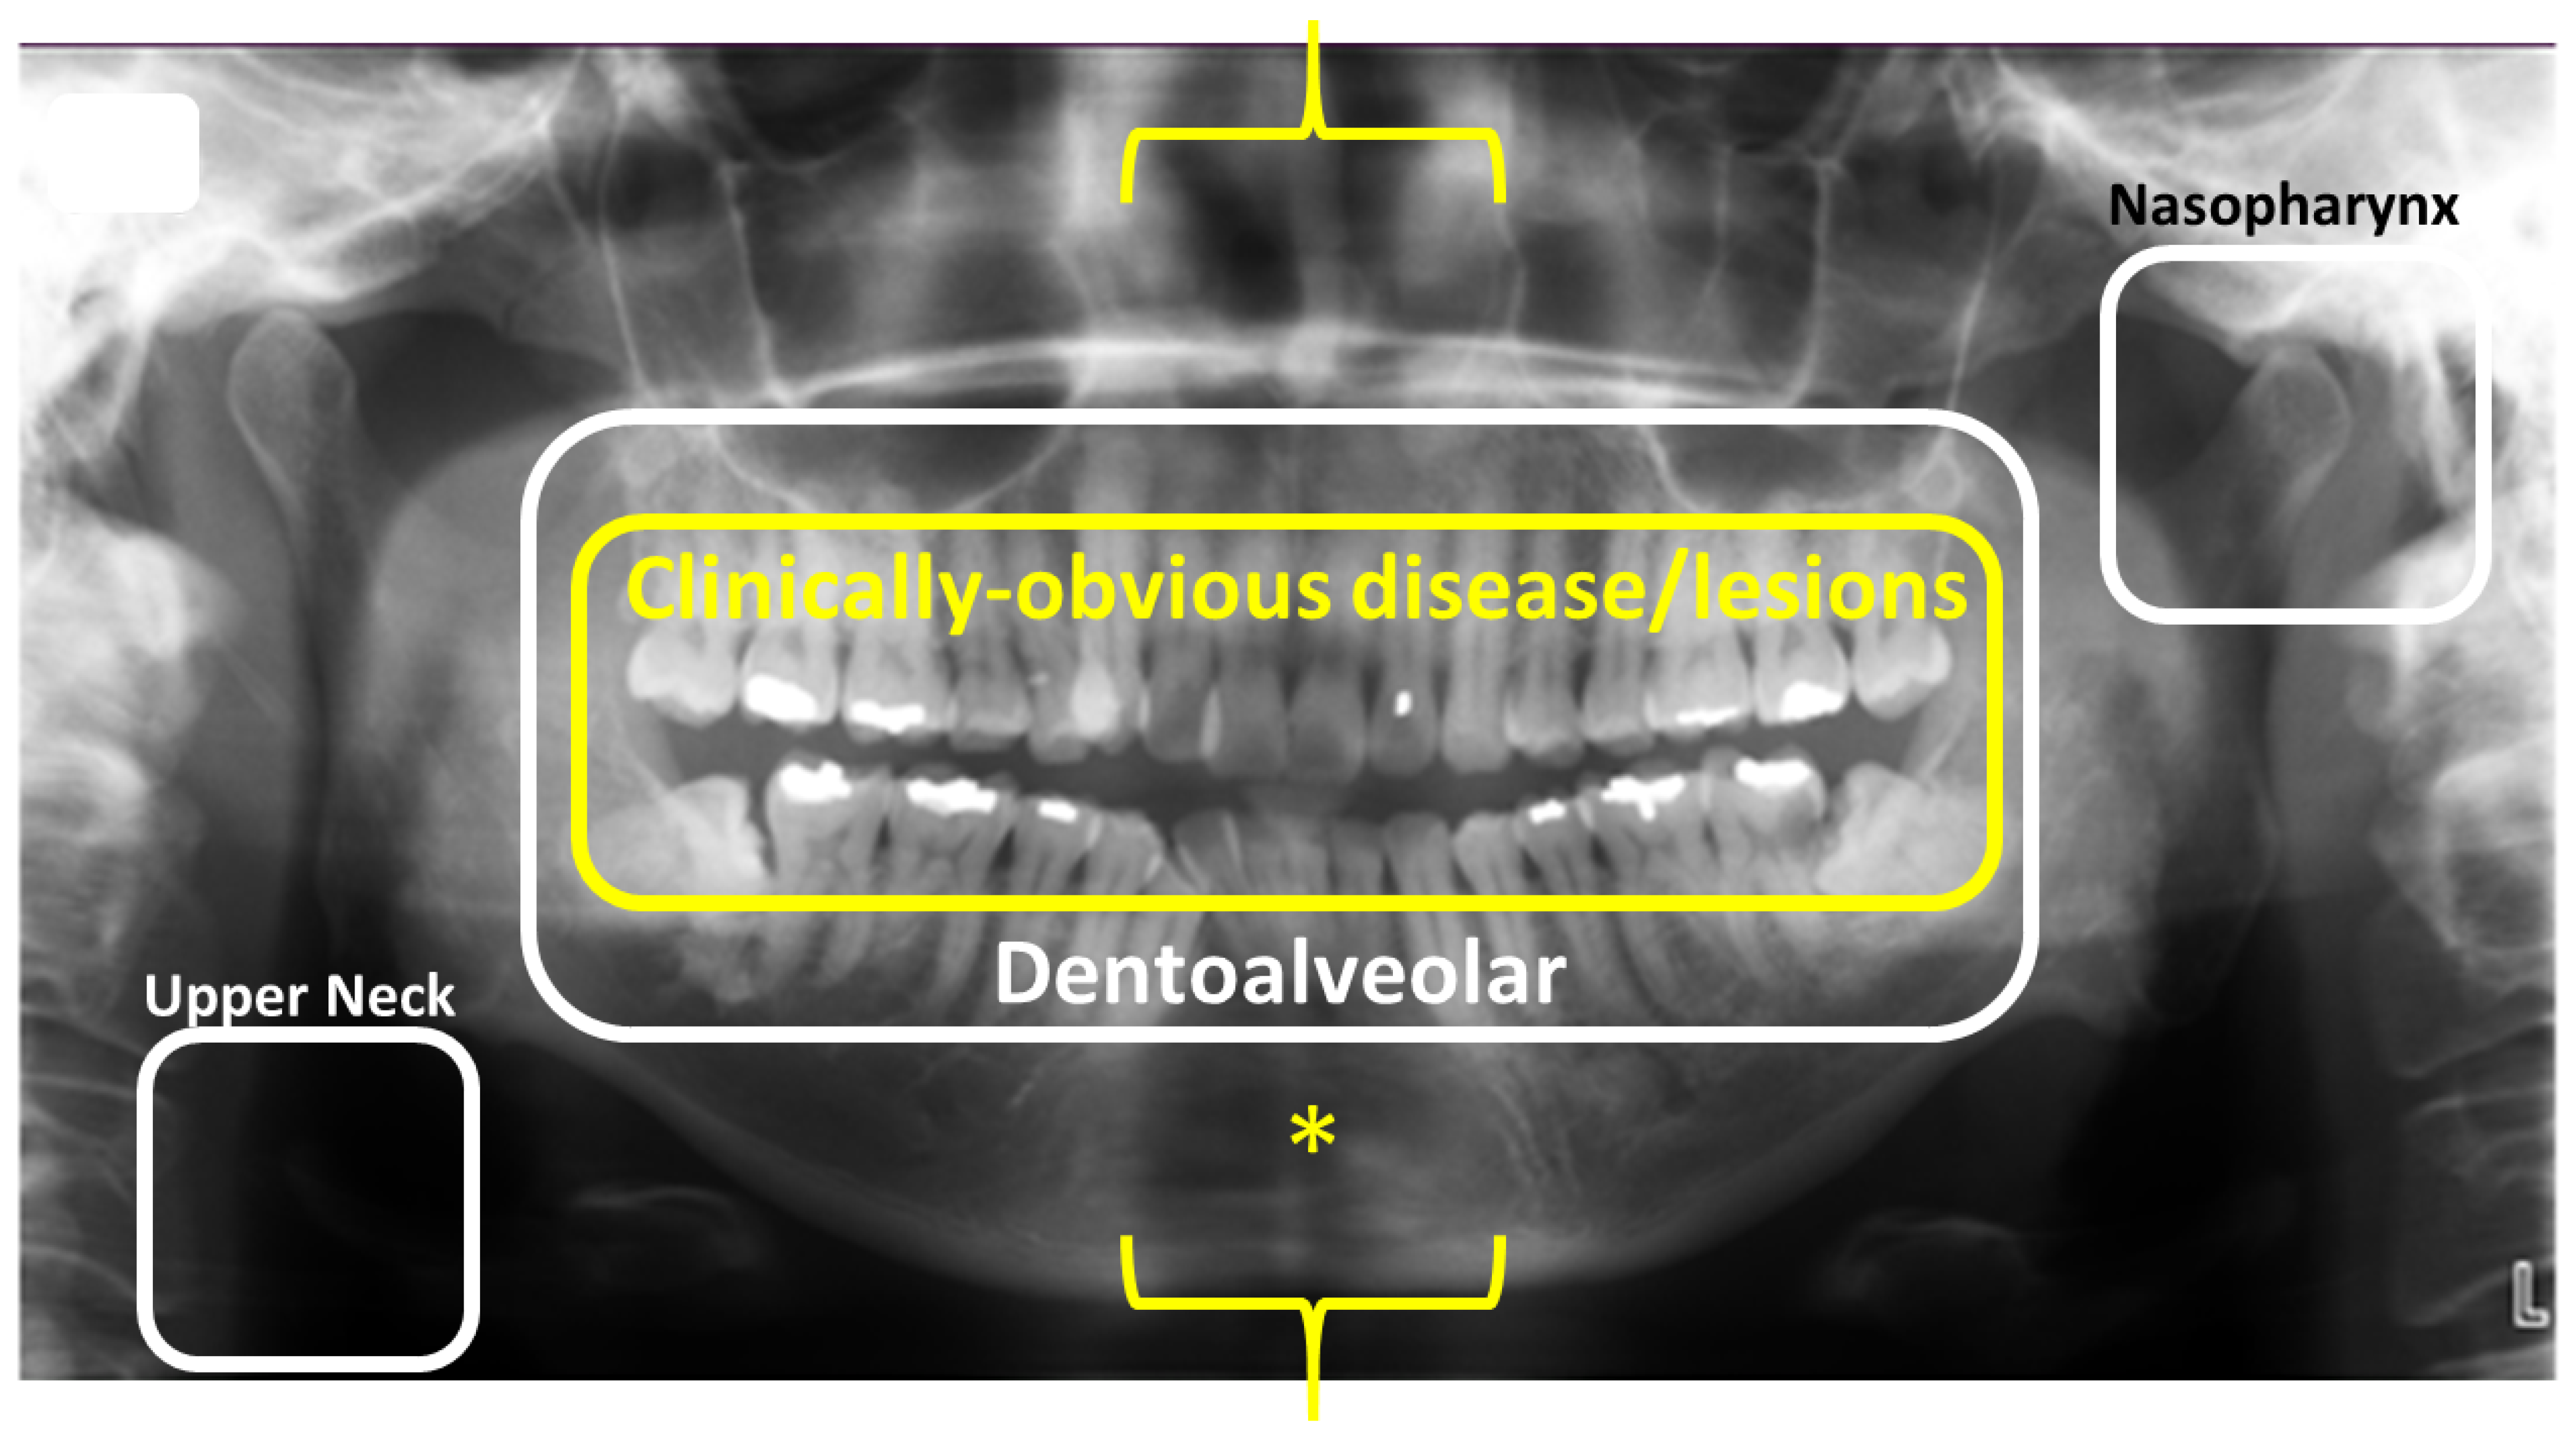

2. Dental Panoramic Radiography

5. Dental Panoramic Radiography—Revisited

Extra-Oral Bitewing